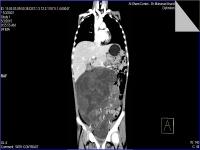

Medical imaging is an important investigative tool will help doctors to reach for the diagnosis of certain diseases, and the the advanced and high-quality imaging technologies are an important factor in maintaining the health of patients and accurate diagnosis of pathological lesions.